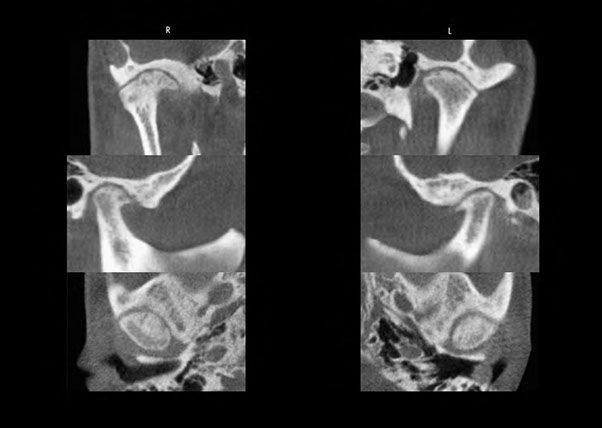

Normal temporomandibular joints